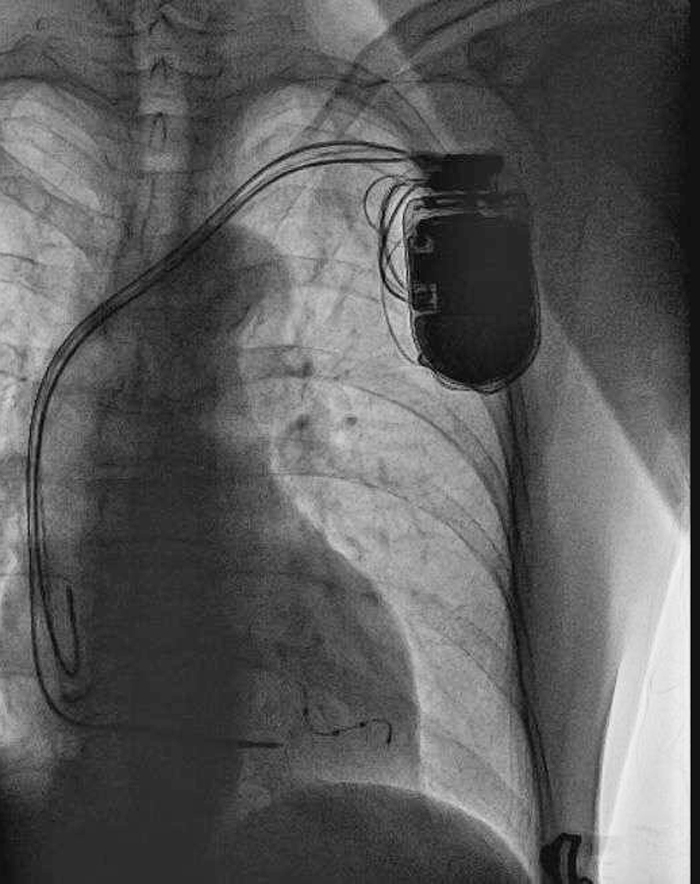

張大媽植入左室四級(jí)CRT-D影像

(照片由心內(nèi)科提供)